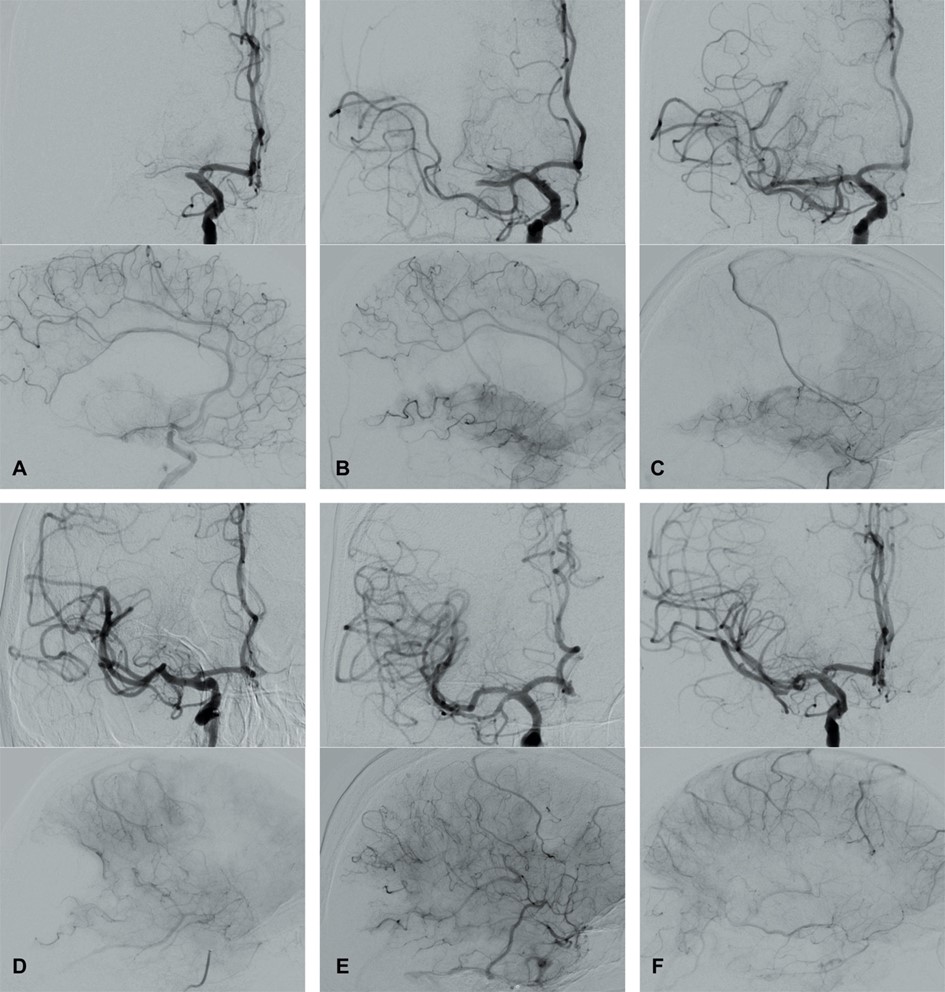

In 2003, Higashida et al. [96] developed the Thrombolysis in Cerebral Infarction (TICI) grading system for evaluating the therapeutic success of IVT (Fig. 4 and Table 3, Ref. [96, 97, 98, 99]). The TICI score is derived from the Thrombolysis in Myocardial Infarction (TIMI) risk score. TICI scores of 0 or 1 indicate no or limited perfusion, respectively. TICI scores of 2a and 2b describe anterograde reperfusion of less or more than half of the occluded target artery previously ischemic territory, respectively. A TICI score of 3 indicates complete reperfusion without any visible distal vessel occlusion. The TICI system has been adapted and modified (mTICI, which is commonly used in both the literature and routine clinical practice) to include an additional TICI 2c category indicating near-complete perfusion except for slow flow or distal emboli in several distal cortical vessels [97, 98]. An excellent reperfusion outcome is defined by mTICI scores of 2c/3. The HERMES collaborators described the expanded TICI (eTICI) score in 2019 [99]. MRS-shift analyses at 90 days after MT have suggested differences in outcomes depending on the percentage of recanalized brain tissue (Table 3). The eTICI has been found to be an independent predictor of outcomes.

Fig. 4.Modified Thrombolysis in Cerebral Infarction (mTICI) grading system for evaluating the therapeutic success of IVT. No perfusion of the right MCA - mTICI 0 (A). Antegrade reperfusion past the initial occlusion with only filling of a temporal branch of the right MCA - mTICI 1 (B). Antegrade reperfusion of only the superior division of the right MCA - mTICI 2a (C). Antegrade reperfusion of more than half of the previously occluded right MCA territory with persistent filling defect parieto-occipital - mTICI 2b (D). Near complete perfusion except for some distal emboli in several distal cortical vessels frontal and occipital - mTICI 2c (E). Complete antegrade reperfusion of the previously occluded right MCA - mTICI 3 (F).